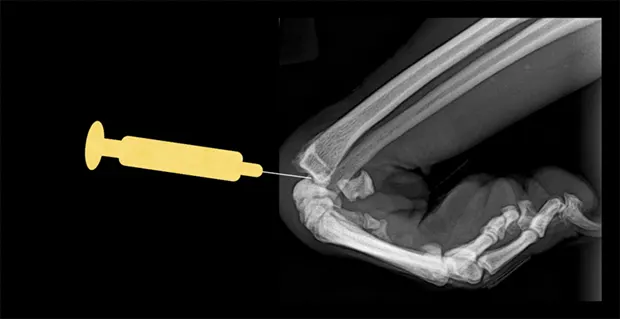

Carpus

Lateral view of carpus. Flex the carpus and insert the needle into the radiocarpal joint just distal to the distal extent of the radius bone.